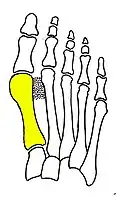

Syndesmosis procedure addresses specifically the two fundamental problems of metatarsus primus varus deformity that gives rise to the bunion deformity. They are leaning and instability of the first metatarsal bone . Syndesmosis procedure uprights the leaning first metatarsal bone with strong binding sutures between it and the second metatarsal bone (Fig. 2) and then also stabilizes it uniquely by creating a fibrous connecting bridge between these two bones (Fig. 3, 4). First metatarsal bone can be readily realigned because by definition of the metatarsus primus varus deformity its first metatarsal is abnormally loose and mobile.